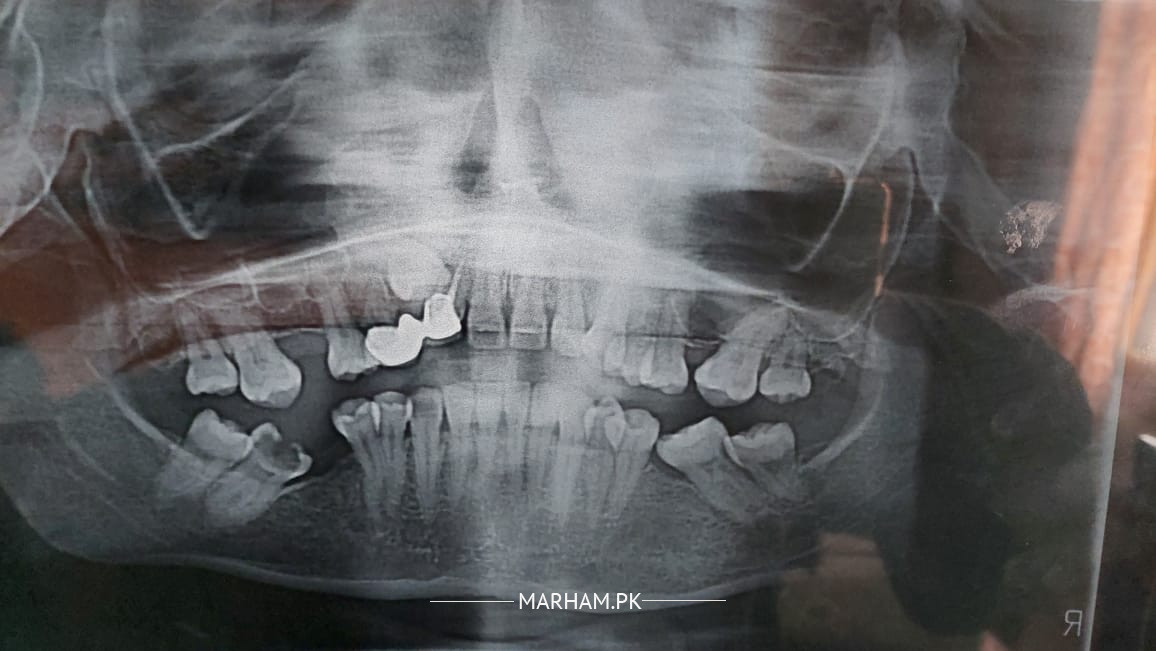

The question is related to impacted canaine teeth. July me braces lagwe the then mid December surgery hoi impacted canain teeth kely surgery ko one and half month hogae dant appear nahi hoa. doctor ka kehnna ha ke agar dant bahr nahi ata to hum dubara surgery ye pochna ha ke kya ye normal ha aik hi dant kelyen dou dafa surgery karna ?mujhe dubara surgery nahi karwana to kya koi behtr option ha stuck teeth kelye.

Please check xrays.

Xrays